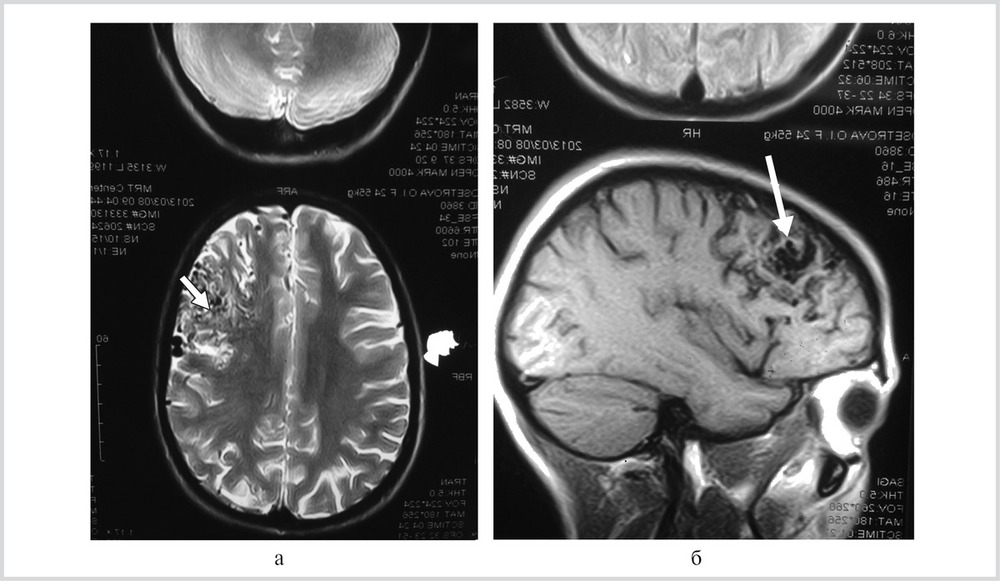

Кроме артериографии, также проводится компьютерная томография. Эти два метода могут комбинироваться, и такой подход называется ангиографией. В этом случае к процессу диагностики подключается рентгеновское излучение. Также широко используется магнитно-резонансная томография, которая является эффективным способом выявления заболеваний.

1. Магнитно-резонансная томография (МРТ)

МРТ является одним из самых информативных методов для диагностики сосудистых мальформаций. Она позволяет получить детализированные изображения мягких тканей и сосудов без использования ионизирующего излучения. Специальные режимы МРТ, такие как МР-ангиография, позволяют визуализировать сосудистую сеть и выявлять аномалии, такие как артериовенозные мальформации (АВМ) и кавернозные ангиомы. МРТ также помогает оценить состояние окружающих тканей и выявить возможные осложнения, такие как отек или геморрагия.